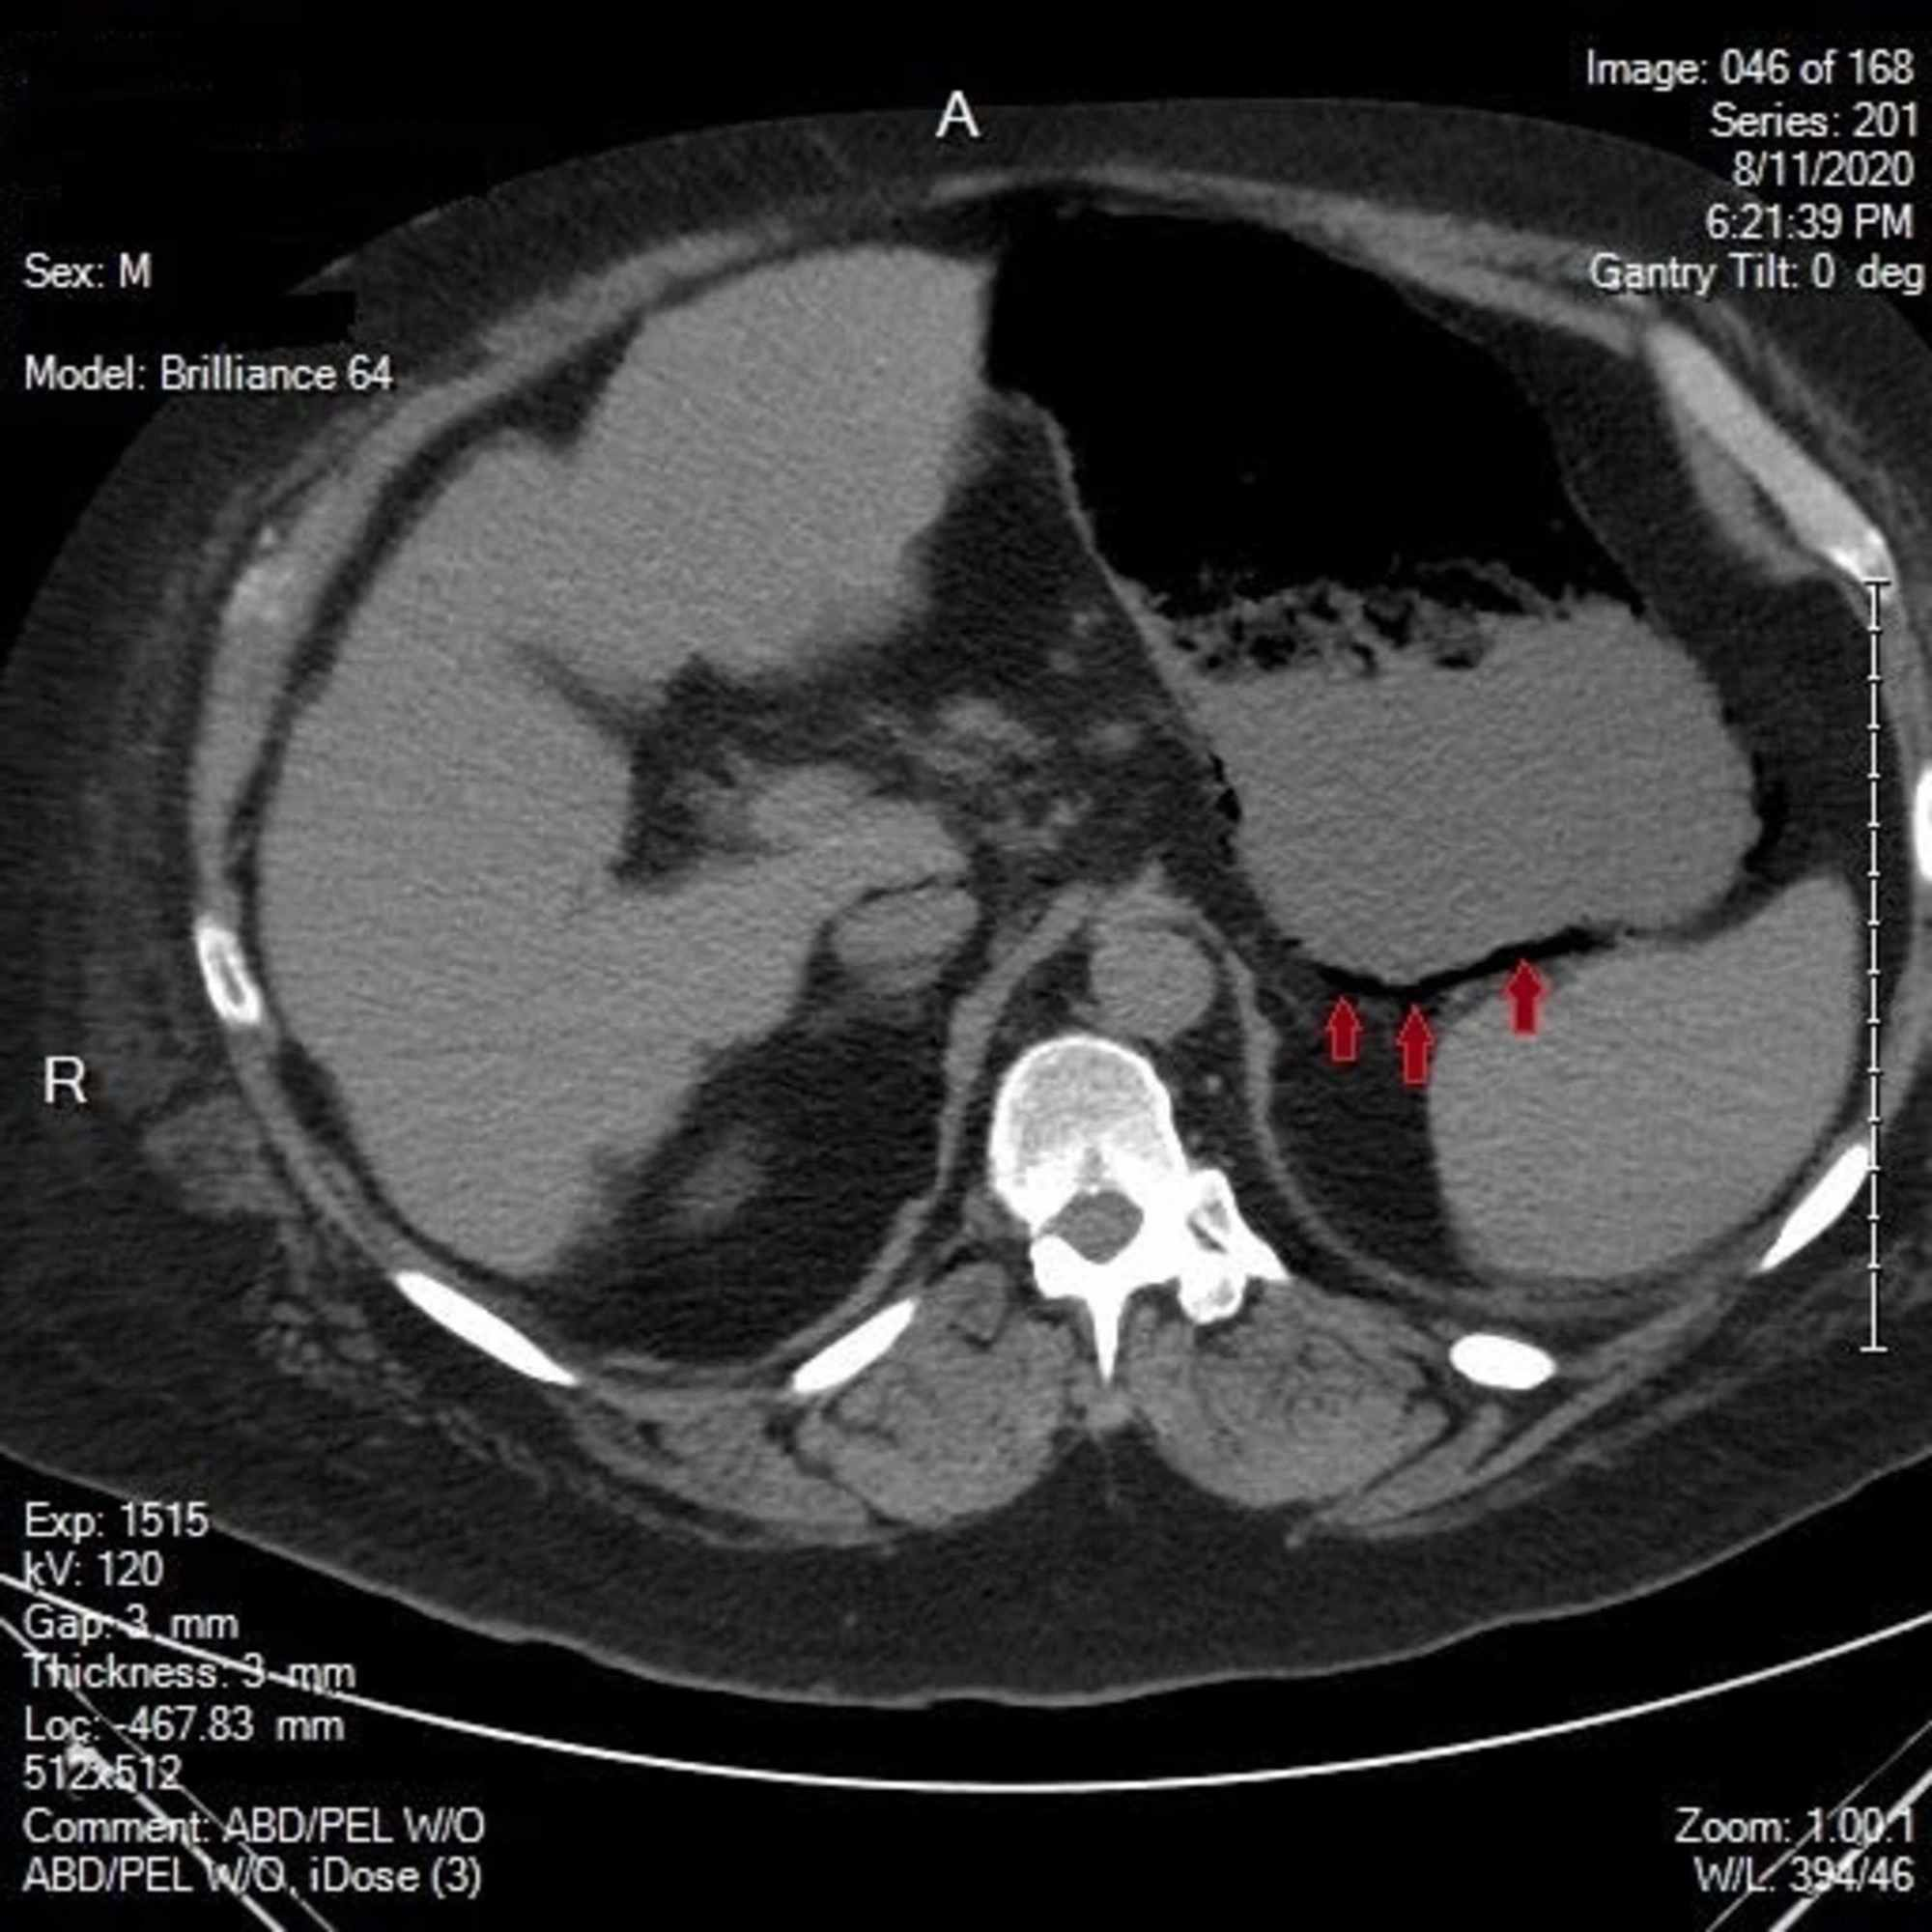

Cureus | Gas in Your Stomach? A Curious Case of Complicated …

Stomach Cancer Ct Scan

CT sagittal. Large amount of perirectal free gas consistent with rectal …